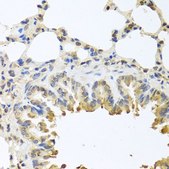

immunofluorescence: 1:50-1:200, immunohistochemistry: 1:50-1:100, western blot: 1:500-1:2000